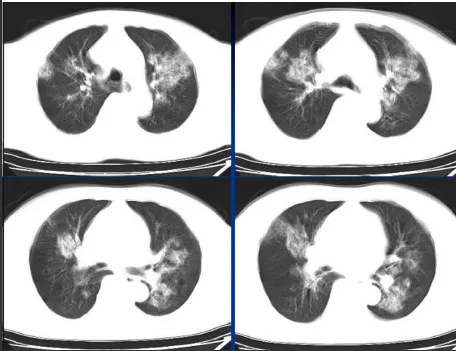

病例:男,33岁,急性肾衰肺水肿。CT表现:①肺间质性肺水肿:两肺血管束增多、增粗,边缘模糊;②肺泡性肺水肿:两肺透光度减低,并见广泛性分布结节样、斑片样密度增高影及毛玻璃样影,边缘模糊,以两肺内、中带分布较明显,形成典型“蝶翼征”;③胸腔积液。